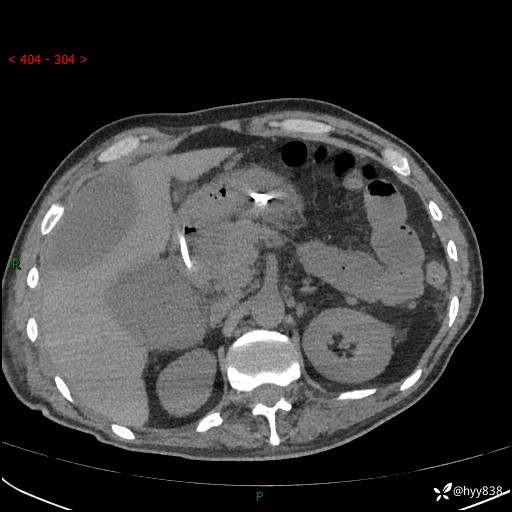

讨论:患者病情稳定后,转ICU,但出现胃瘫、持续发烧,找不到原因

腹部CT平扫

增强